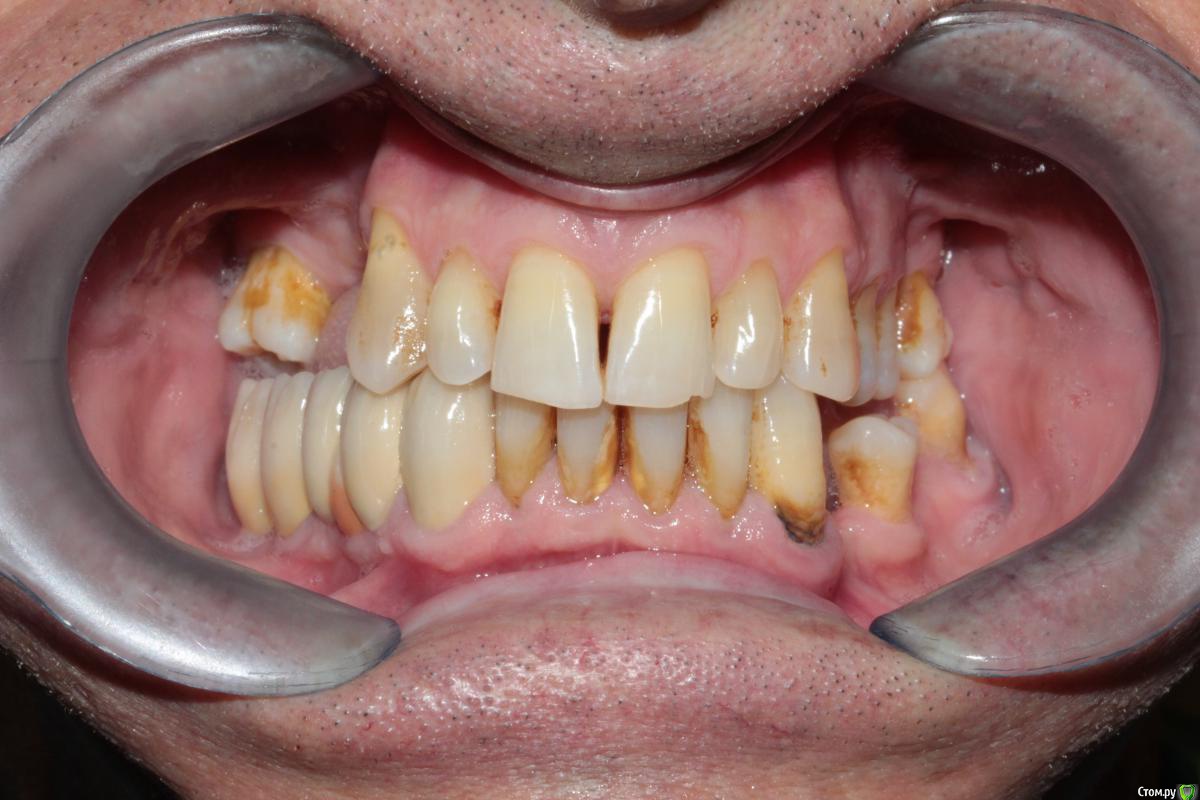

Здравствуйте уважаемые коллеги. Прошу у Вас совета какой план лечения вы бы рекомендовали данному пациенту.

Сразу замечу, я сначала рассматривал вариант с ортодонтией (чтобы собрать все зубы вместе) а далее в отсутствующие места имплантация. Но, пациент не в силах оплатить это лечение. Так как пациент мой бывший учитель, я хочу ему помочь, сделать работу которая материально минимально затратна и функционально его обеспечит.

37ой зуб я уже удалил, сначала сделал ревизию, обнаружен был кариес корня по фуркации, поэтому удалили. На данный момент пациент не может полноценно жевать.

Меня больше смущает 2 момента, 1й - это то что на верхней челюсти зубы "разбросаны" как попало, не знаю что можно сделать не собрав их вместе предварительно. 2ой - в 4ом сегменте мост, консольный, его снимать не хочется, так как его по сути недавно поставили, а не сняв его не знаю что можно сделать в 3ем сегменте, если имплантацию откидываем как вариант....

Был предложен вариант сделать бюгель, с обычными кламмерами на верхней челюсти, как думаете при таком расположении зубов, это правильно?

P.S. - не совсем понятно как получилось  так, что фронт в контакте а премоляры вне контакта (слева).